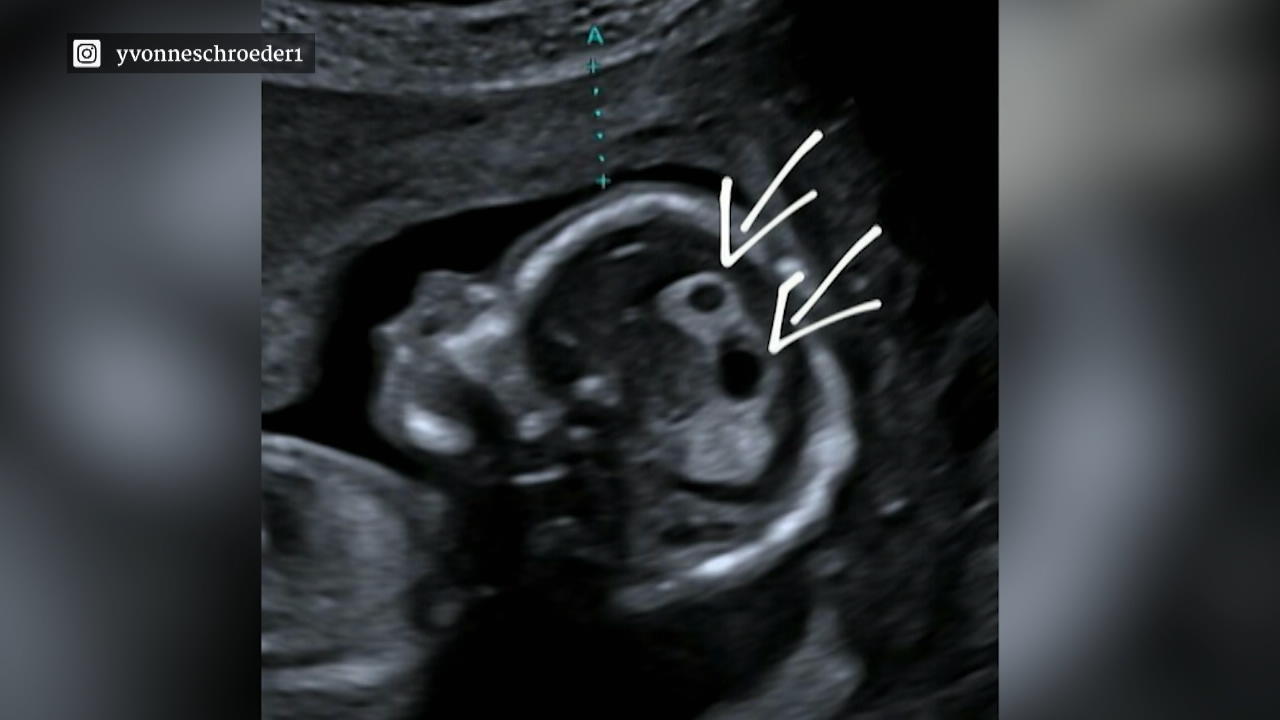

Yvonne Schröders ungeborenes Baby hat Zysten im Kopf

Eigentlich sollte diese Nachricht nichts als pure Freude auslösen: Model Yvonne Schröder und Fußballstar Tim Kister erwarten ihr drittes Kind. Doch eine besorgniserregende Diagnose lässt die Vorfreude auf ihr Baby trüben.